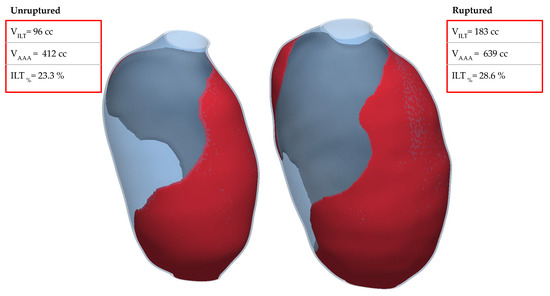

2.1. Clinical Case